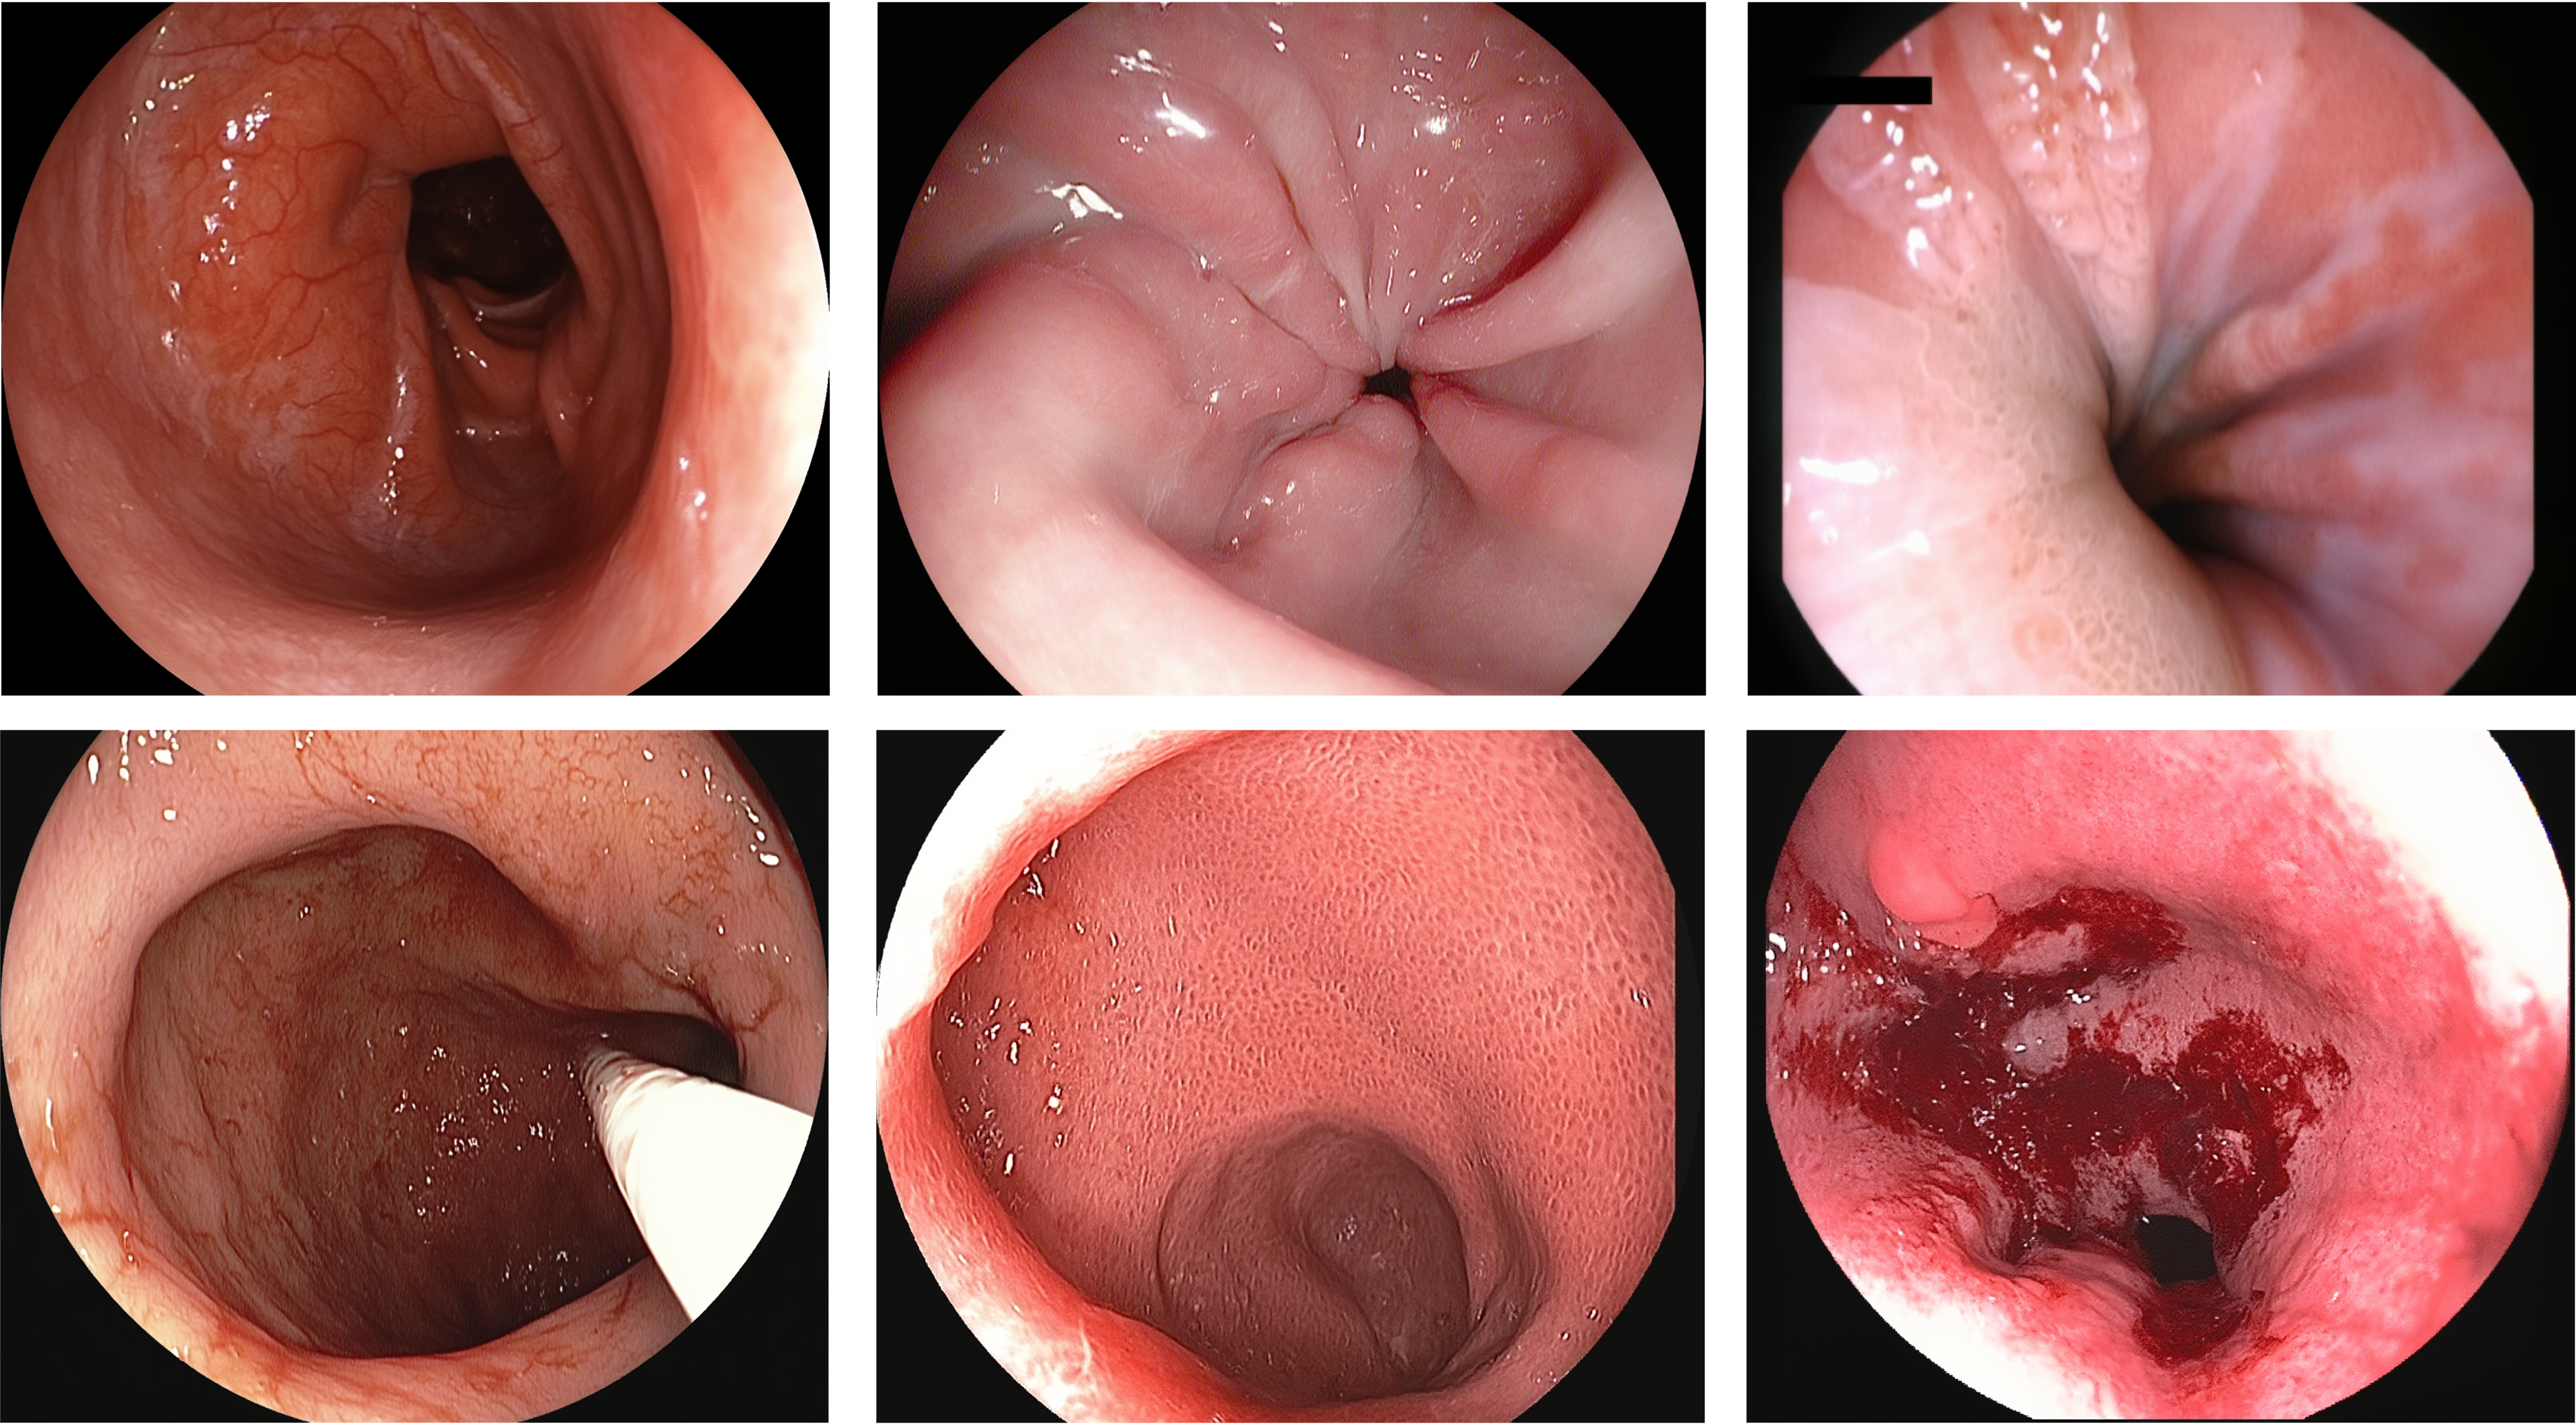

Text-to-medical-image generation results showing high-quality synthesis

Additional text-to-medical-image generation examples across modalities

Medical-Image Generation across 8 modalities

Endoscopy